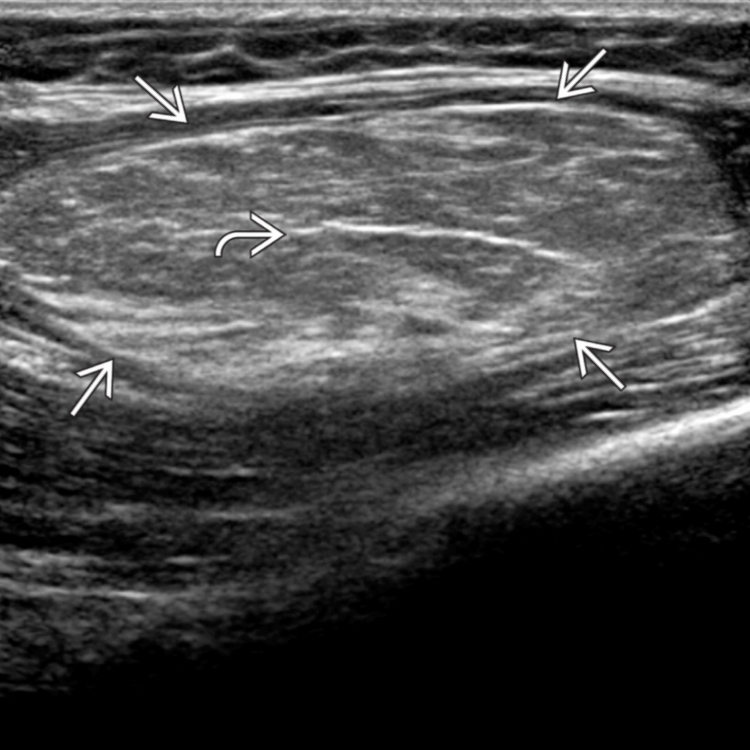

Lipoma of the spermatic cord. (a) US image demonstrates an echogenic …

Lipoma MRI – wikidoc

Lipoma | Radiology Case | Radiopaedia.org

Lipoma | Radiology Case | Radiopaedia.org